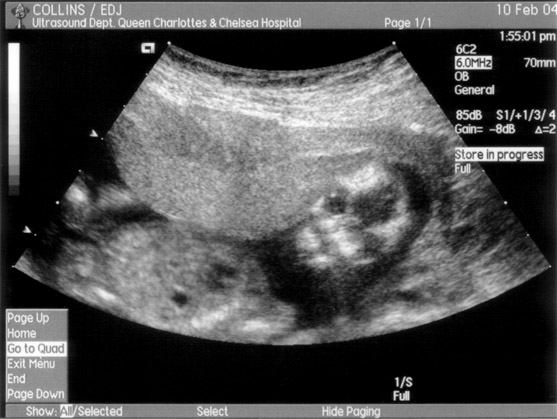

These are the first pictures of our new baby, (due on the 4th August), taken during Tracey's first ultrasound scan on 10th February.

In this one the baby is look straight towards us, (freaky!):